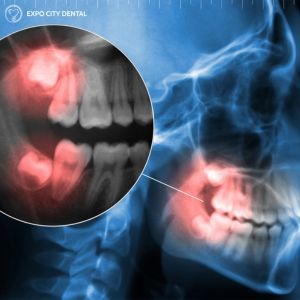

Signs of Impacted Wisdom Teeth

Some approximations estimate that about 85% of Canadian adults will have had a wisdom tooth extraction at some point during their life. From managing pain and preventing infection to reducing the chances of changes in your bite, there are a number of reasons why dentists in Vaughan will recommend you undergo wisdom teeth removal procedures. Removal is typically an option when the molars are...

Wisdom teeth removal is a widespread dental procedure that dentists in Vaughan typically recommend in early adulthood or adolescence. As the wisdom teeth erupt from the gums, they can cause a number of problems, from shifting your teeth, becoming impacted, triggering serious pain, or even becoming infected. At Expo City Dental, Dr. Farzin and our team provide wisdom teeth removal in Vaughan so you...